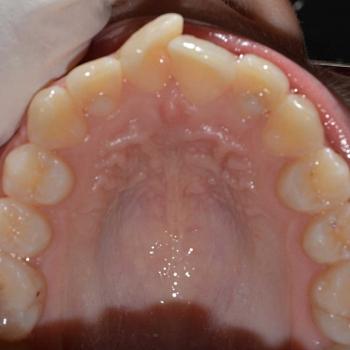

Eszter és édesanyja az iskolai fogorvosuk javaslatára kerestek fel, mert a kolléga, az esztétikai problémát okozó torlódás mellett, Angle II. osztályú funkciós eltérést is tapasztalt. Szerencsére ezeken felül egyéb eltérésre a konzultáció alkalmával sem derült fény.

Eszter a kezelés megkezdésekor headgear típusú fogszabályozó készüléket kapott annak érdekében, hogy a felső nagyőrlőket hátrafelé mozgassuk, illetve, hogy a keletkező rést felhasználjuk a kisőrlők és a szemfogak hátramozdítására is. Az így felszabadult hely az Eszter által választott hagyományos fém fogszabályozó segítségével felhasználható volt a metszőfogak elrendezéséhez, azok túlzott előredőlése nélkül.

A kezelés eredményeként minden kiindulási problémát sikerült megoldani és egy esztétikailag és funkcionálisan is szép mosolyt létrehoznunk.